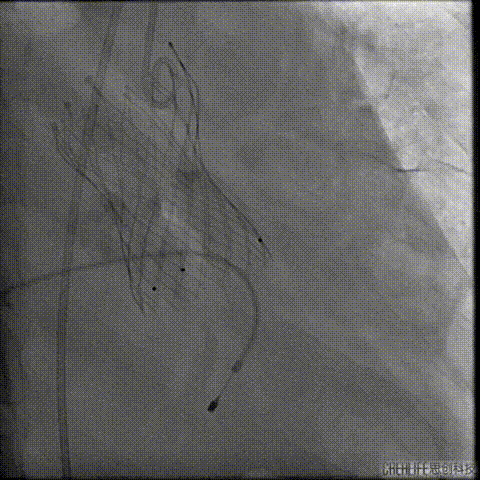

经桡冠脉保护

置入Venus-A32号瓣膜并释放

复查造影

撤出冠脉保护

再次复查造影

经瓣架网眼挂上指引管

反复确认指引管经瓣架网眼

指引管经瓣架网眼

经网眼置入导丝